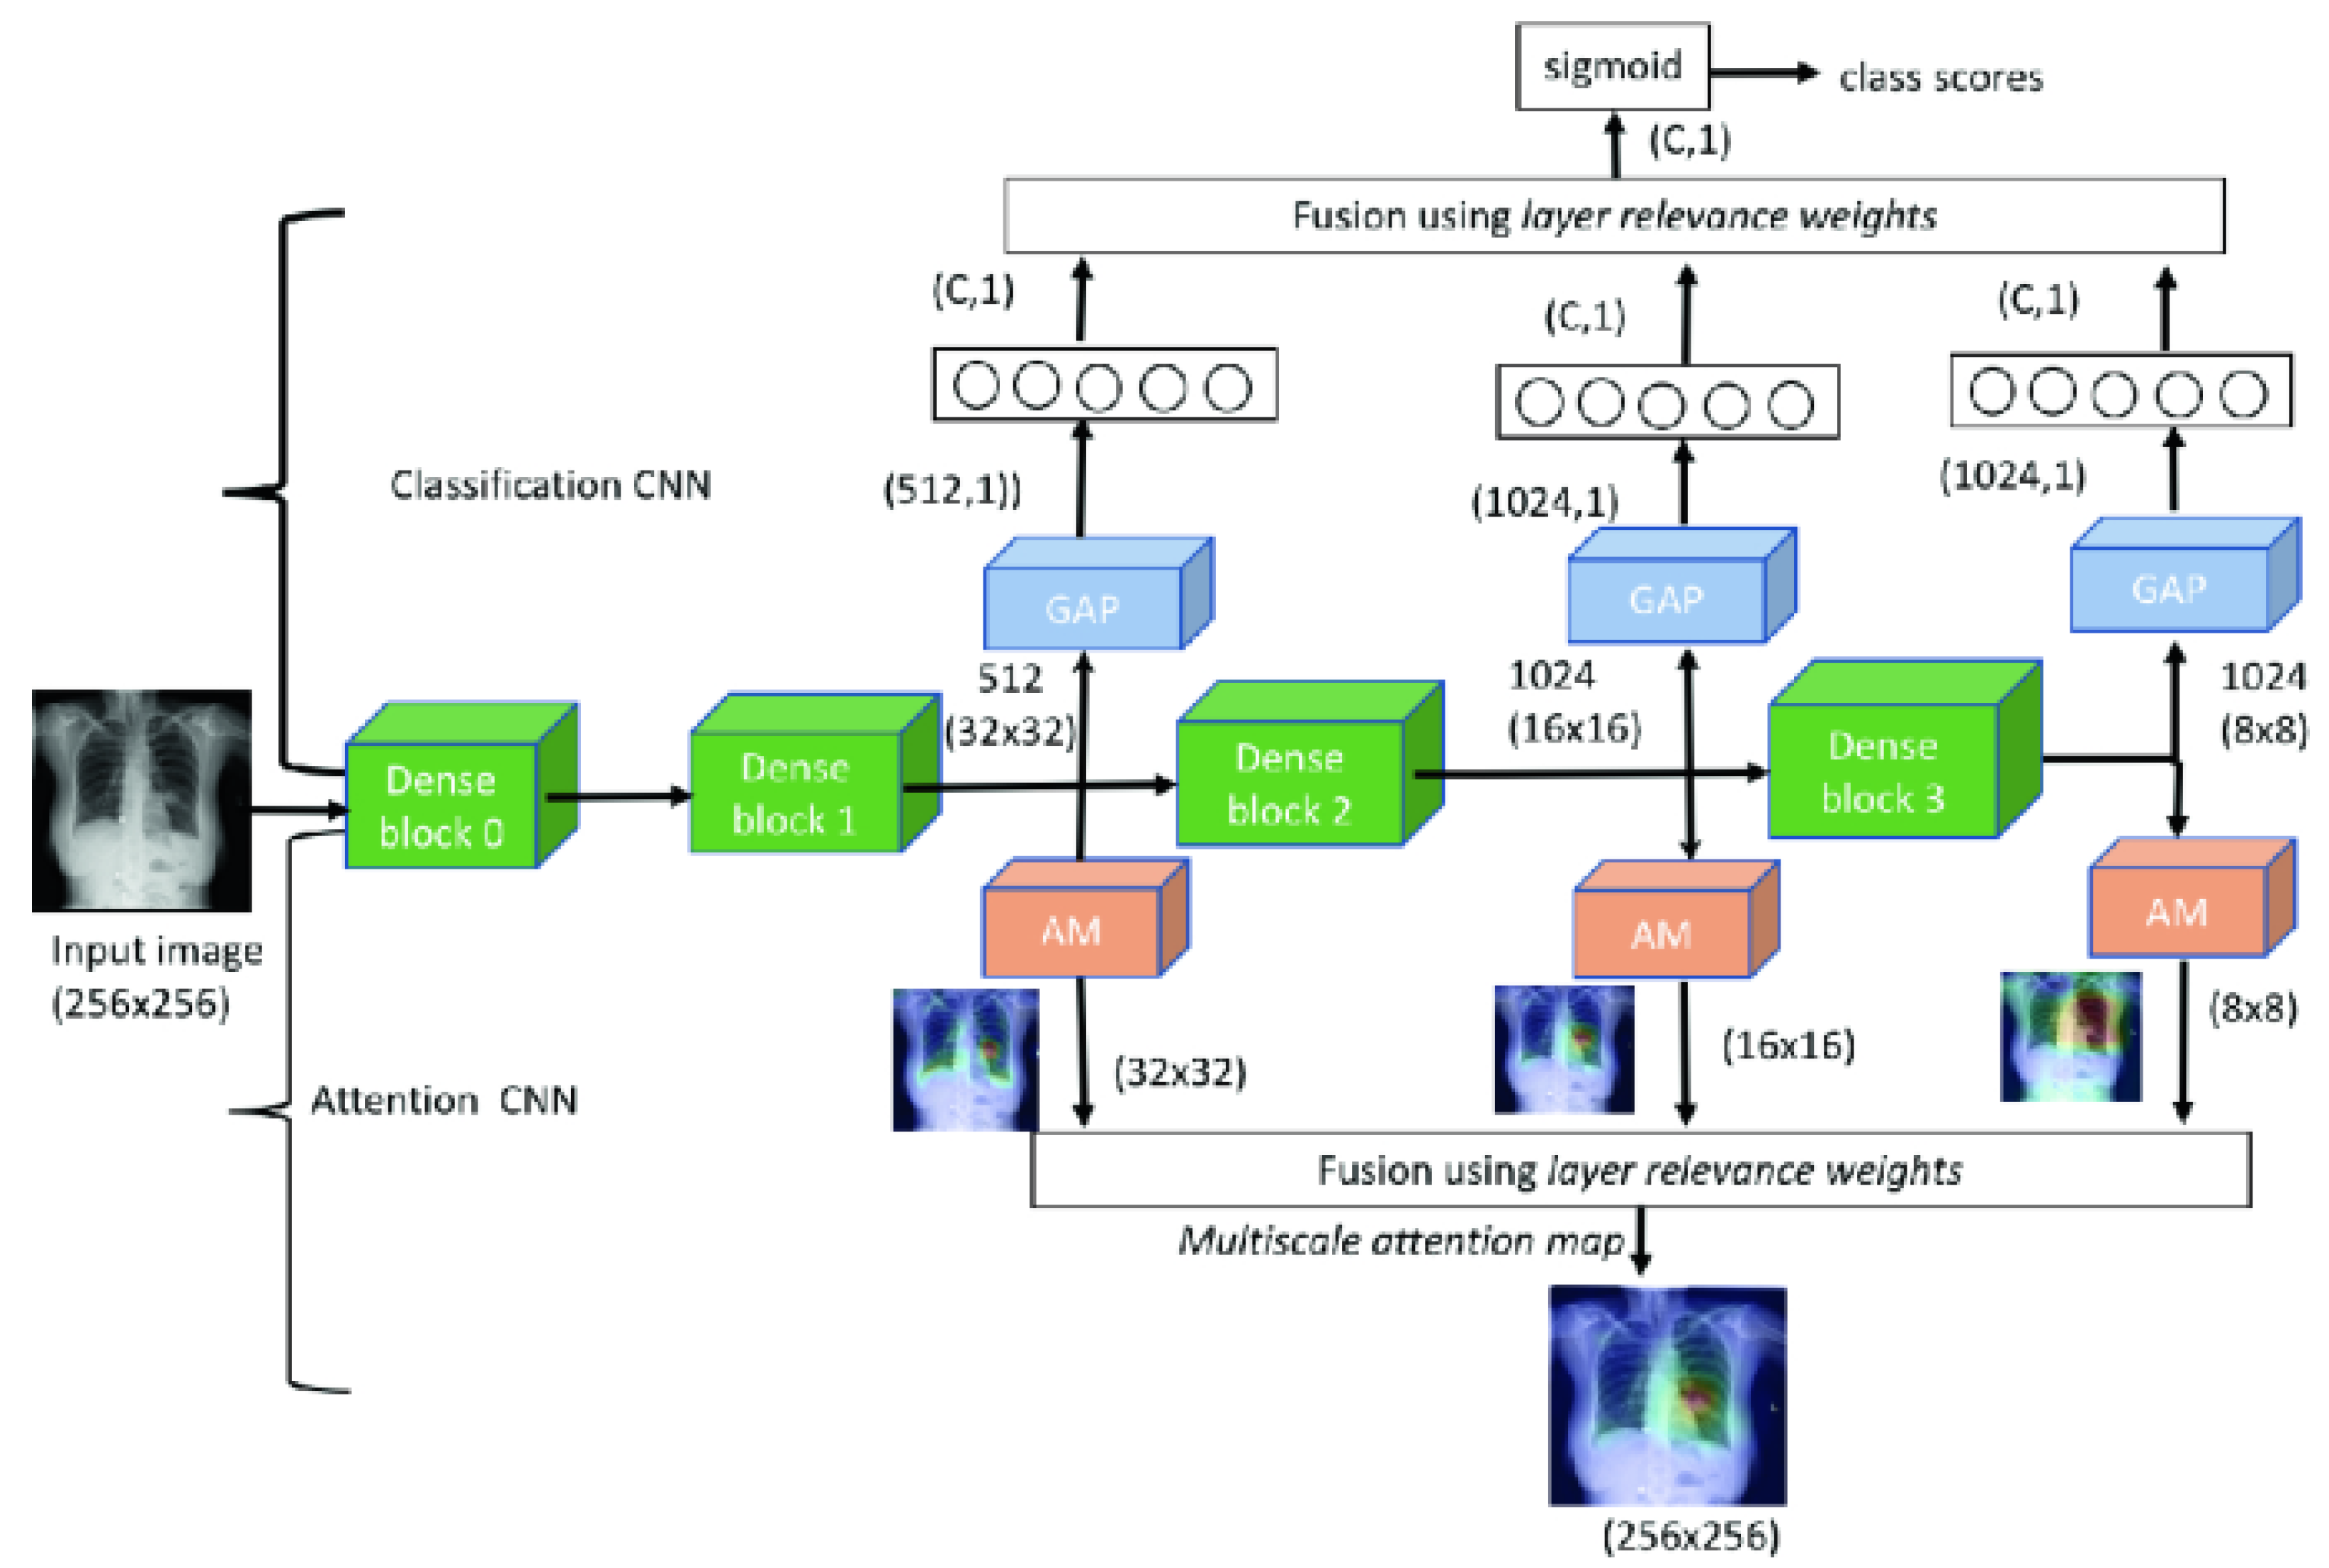

| Seda et al., 2018 [103] | ChestX-ray14 | Multiscale attention map and layer relevance weights |

| Singh et al., 2020 [106] | The posteroanterior CXRs from Christian Medical College in Vellore, India | Multiscale attention map |

- Sedai, S.; Mahapatra, D.; Ge, Z.; Chakravorty, R.; Garnavi, R. Deep multiscale convolutional feature learning for weakly supervised localization of chest pathologies in X-ray images. In Proceedings of the International Workshop on Machine Learning in Medical Imaging, Granada, Spain, 16 September 2018; pp. 267–275. [Google Scholar]